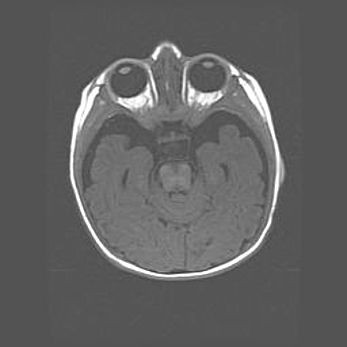

Неполная лизэнцефалия (пахигирия). Открытая гидроцефалия.

Возраст: 17 дней

Вес: 3110 г

Пол: мужской

Окружность головы: 33,5 см

Срок гестации: 35-36 недель

Лизэнцефалия—недоразвитие корковой пластинки и мозговых извилин в результате нарушения миграции нейронов коры. Поверхность мозговых полушарий гладкая. Микроскопически выявляется отсутствие нормальных слоев коры и скопление групп нейронов в подкорковом белом веществе.

Пахигирия—уменьшение числа вторичных извилин. В пораженном полушарии нервные клетки образуют толстый недифференцированный слой с неправильно расположенными нервными волокнами и группами гетеротопных клеток. Нервные клетки незрелые. Белое вещество истончено. При этом нередко аномально развит корково-спинномозговой путь.